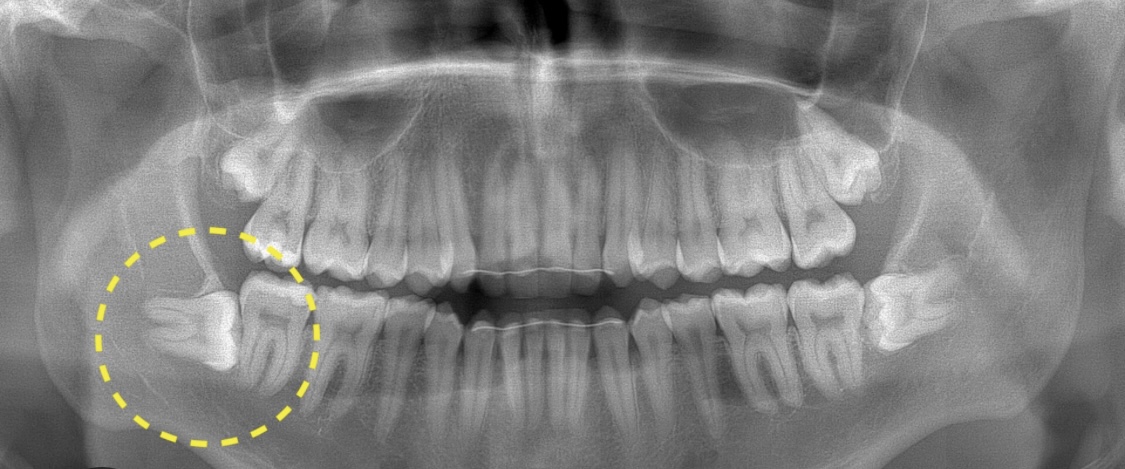

Сегодня сделали панорамный снимок,у меня восьмерки лежат с обеих сторон,срочно нужно удалять их😭

Я вот не рискую во во время беременности удалить ,на фото такое же как у вас два зуба Бьют в остальные